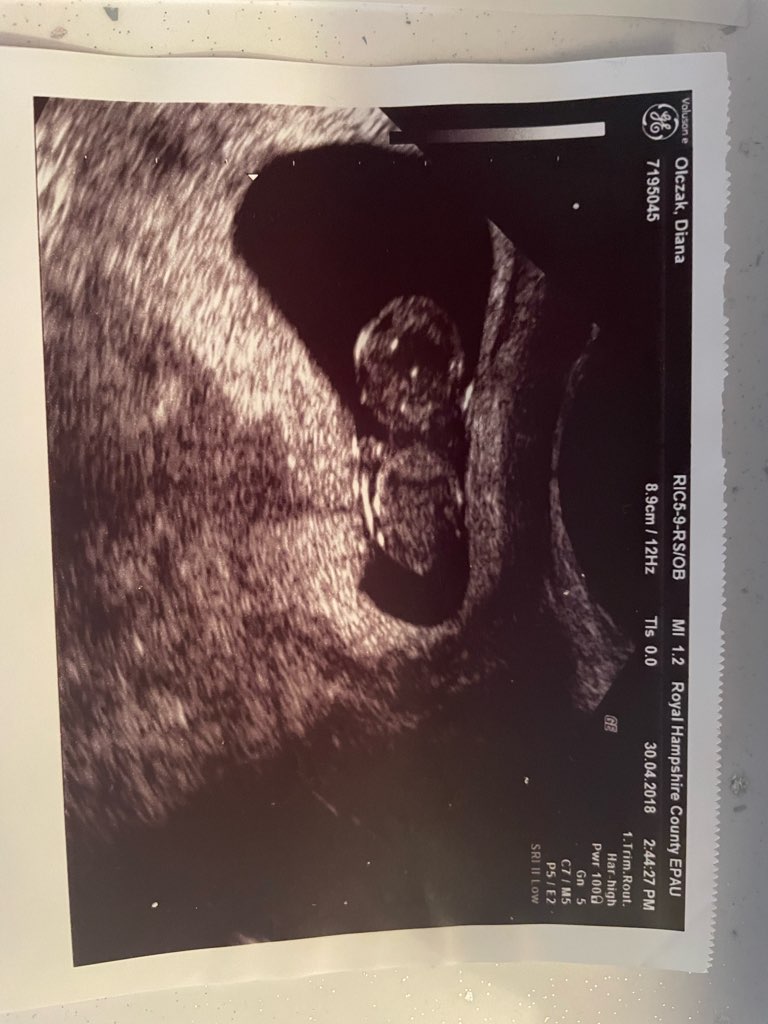

Na pewno Cię nie pogoni. Ja też bylam w 5+4 na pierwszej wizycie i było serduszko. Nawet jak u Ciebie nie będzie jeszcze serduszka to przynajmniej będzie wiadomo, że pęcherzyk jest na swoim miejscu.

1 zdjęcie z 5+3 (2.7mm)